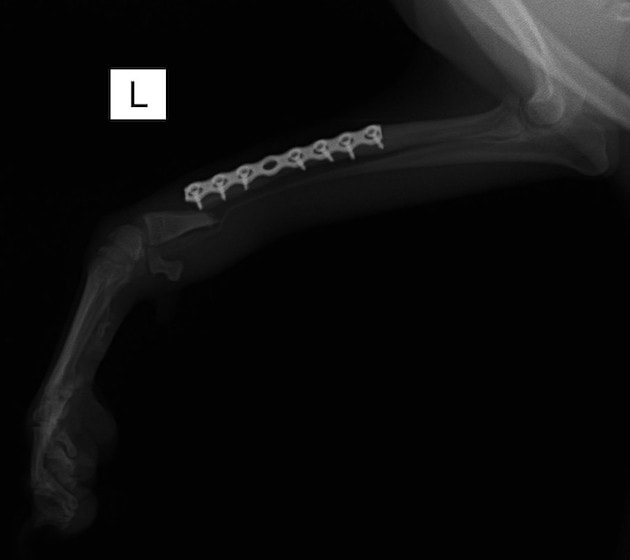

トイプードル 右遠位橈尺骨短斜骨折のALPSによる内固定